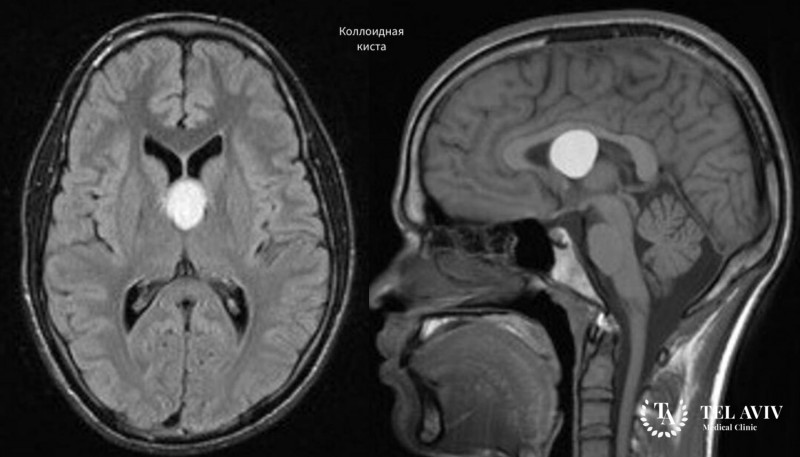

Коллоидные кисты относят к классу опухолевых образований в головном мозге человека. Они имеют округлую форму, поражают третий желудочек мозга, его полость. Согласно исследованиям, кисты возникают по причине нарушений в развитии нервной системы в период формирования плода. Нормальное развитие мозга ребенка страдает от негативного воздействия внешней среды:

Размер коллоидной кисты на начальной стадии не превышает несколько миллиметров. Триггерные факторы стимулируют рост образования. Опухоль увеличивается быстрыми темпами.

Диагностик коллоидной кисты начинается с первичного опроса, осмотра пациента. После сбора анамнеза специалист направляет больного на дополнительные анализы. Наиболее результативными признаны следующие методы обследования:

- Магнитно-резонансная томография;

- Компьютерная томография с использованием контрастного вещества;